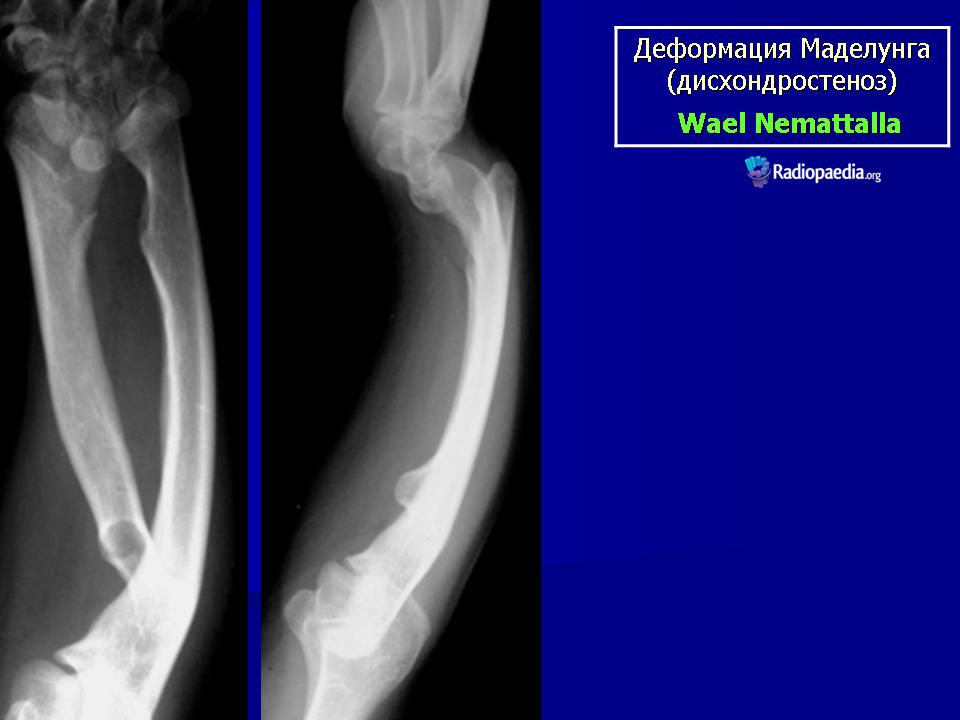

Диагноз устанавливают на основании характерных клинических и рентгенологических проявлений. При рентгенологическом исследовании выявляют относительное укорочение лучевой кости на 4—5 см и скошенность суставной поверхности дистального эпифиза лучевой кости в ладонную и локтевую сторону, что создает впечатление подвывиха кисти (костей запястья). Полулунная кость как бы нависает над ладонным краем эпифиза лучевой кости. Высота дистального эпифиза по лучевой стороне значительно превосходит его высоту по локтевой стороне, а раннее закрытие эпифизарной ростковой зоны по локтевой и ладонной стороне создает ладонный и локтевой наклон суставной поверхности. Отмечают изменение расположения проксимального ряда костей запястья, они образуют клин, на вершине которого располагается полулунная кость. Головка локтевой кости находится в положении вывиха (в дистальном направлении) и смещена в тыльном направлении относительно лучезапястного сустава. Обычно расположена на уровне основания пястных костей.